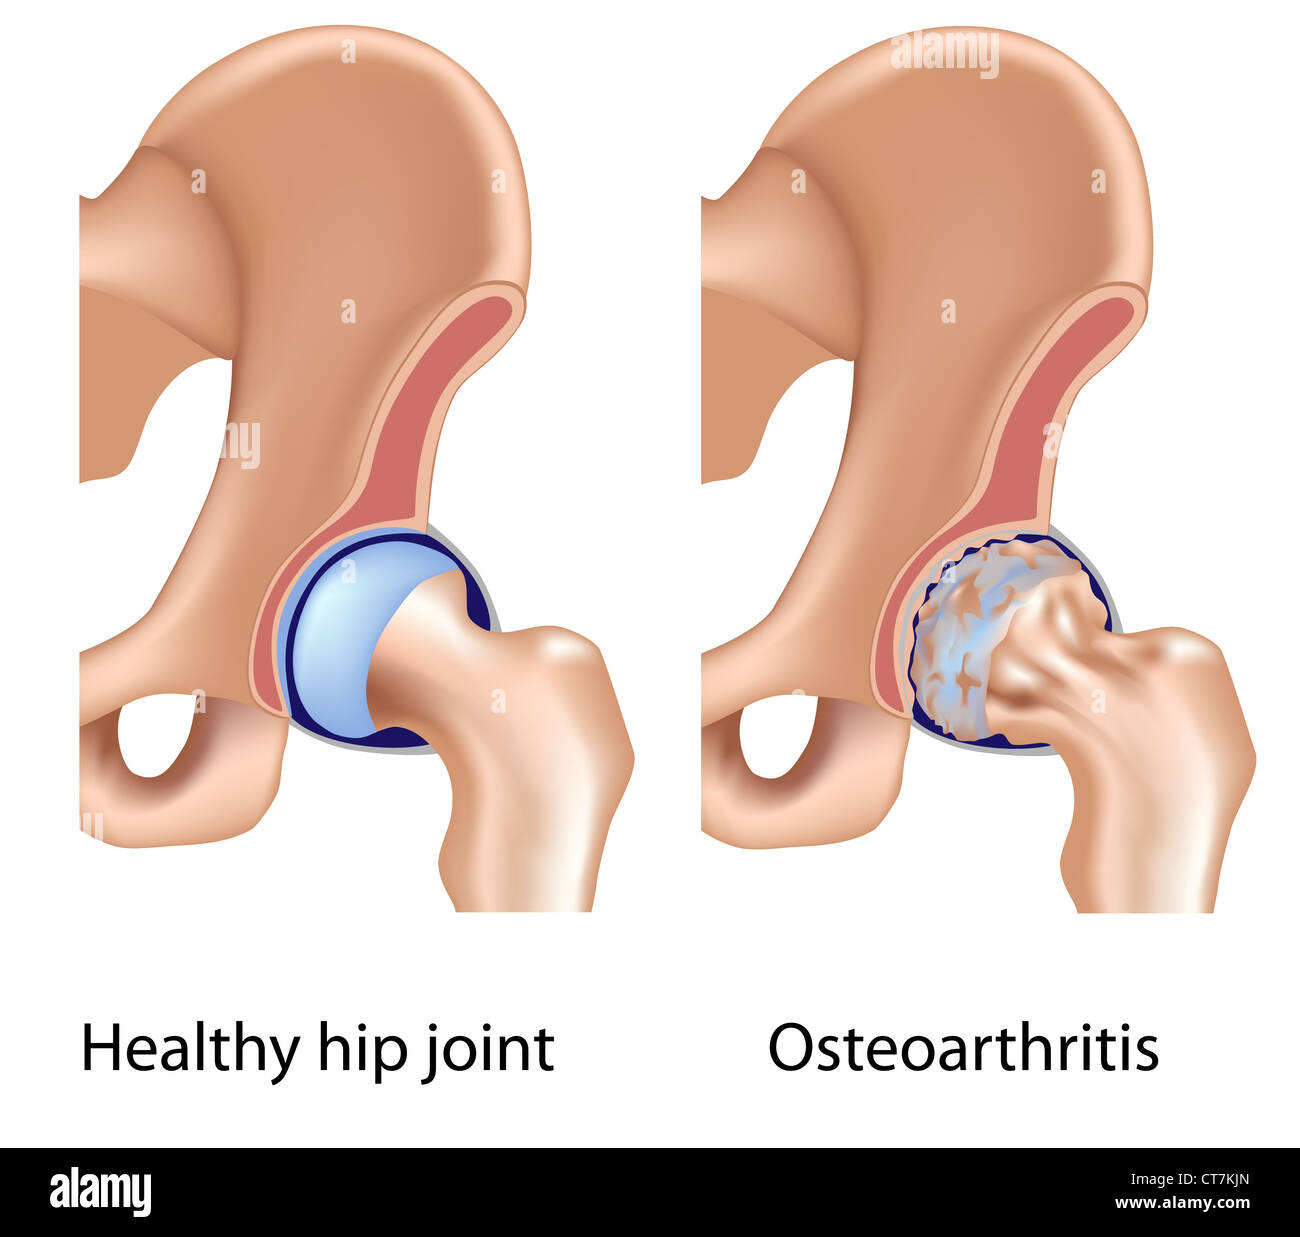

Osteoarthritis of hip joint Stock Photohttps://www.alamy.com/image-license-details/?v=1https://www.alamy.com/stock-photo-osteoarthritis-of-hip-joint-49341565.html

Osteoarthritis of hip joint Stock Photohttps://www.alamy.com/image-license-details/?v=1https://www.alamy.com/stock-photo-osteoarthritis-of-hip-joint-49341565.htmlRFCT7KJN–Osteoarthritis of hip joint